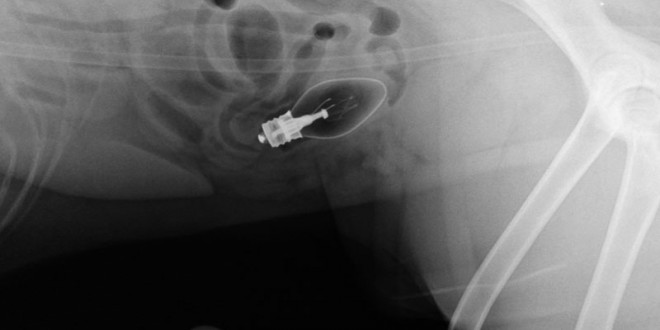

收好你的襪子、黃色小鴨跟燈泡!不然它們會出現在你家毛小孩胃裡!